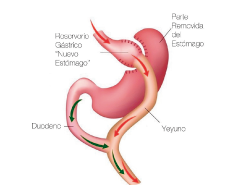

Bypass Gástrico

Es la cirugía con mejores resultados en cuanto a la pérdida de peso y con mayor control de las comorbilidades asociadas a la obesidad, la cual está indicada para pacientes con Obesidad Grado II asociada a otras enfermedades o pacientes con Obesidad Grado III o mayor. Este procedimiento es mediante mínima invasión por laparoscopía, en la que se realiza la formación de un nuevo estómago con una capacidad de 30 - 60 ml, permitiendo tener un efecto restrictivo disminuyendo la ingesta de alimentos y por otro lado se aisla la porción del estómago que produce hormonas que generan hambre por lo que se reduce sustancialmente el apetito. Este nuevo estómago se conecta con un asa intestino delgado, llamada “Asa alimentaria” por la cual transita el alimento ingerido y distalmente se une a otra asa intestinal por la que transita de forma normal bilis y enzimas pancreaticas; sin embargo es hasta que se unen estas dos, en una asa intestinal común cuando se lleva a cabo la absorcion de los nutrientes, de este modo es como se lleva a cabo otro efecto del Bypass Gástrico en la reducción de peso mediante una mala absorción.

El Bypass Gástrico, es una cirugía con mejores resultados en la pérdida de peso y con mejor efecto metabólico permitiendo el control o remisión total de enfermedades como Diabetes Mellitus, Hipertensión Arterial o Dislipidemia. Un punto crucial en este tipo de cirugías es la seguridad, es por ello que llevamos a cabo este procedimiento con la mejor tecnología de material quirúrgico y realizamos pruebas de las uniones gástricas e intestinales mediante endoscopía, reduciendo al máximo la posibilidad de que se presente alguna complicación y permitiendo que el paciente inicie dieta líquida y se movilice fuera de cama el mismo día de la cirugía y sea egresado a las 48 horas de la cirugía en perfectas condiciones, incorporandose a sus actividades a la semana de la cirugía. Los resultados pueden variar en cada paciente y pueden estar determinados por el apego de los pacientes a las indicaciones médicas.